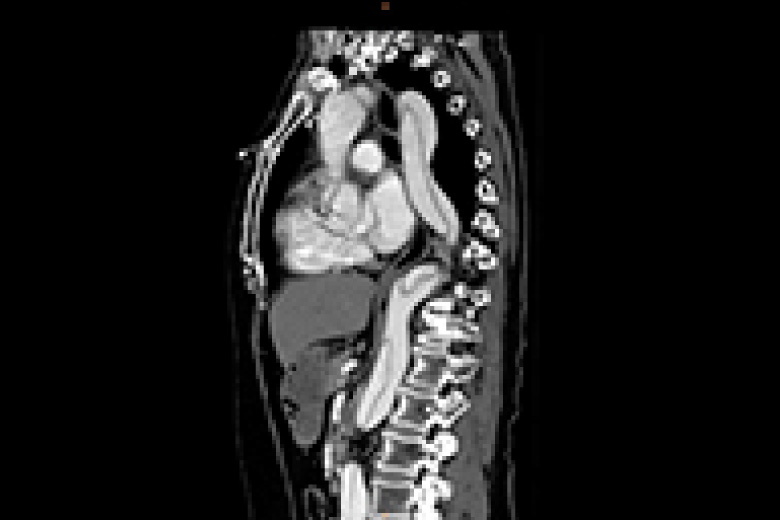

放射線治療

放射線治療とは身体できた病巣部に放射線を照射しがん等の病気を治す治療法です。

手術と比較し身体への負担が少なく病巣部を安全かつ効果的に治療することができます。

当院で使用する放射線は高エネルギーX線及び電子線で直線加速器(リニアック)を用いて人工的に放射線を作るため目的に応じた線質、強さ、量に調整することができます。

実際の治療ではまず治療開始前にCT撮影を行い、照射する場所、範囲、放射線の量等を専用の機器を用いて決定します。(下図参照)これをもとに治療時には装置に搭載されたX線撮影装置、CT装置にて画像を撮影し3次元的に位置照合を行い計画された方向より照射します。

治療装置は360度どの方向からでも照射可能で病巣を多方向から正確に照射することで治療効果の向上、病巣周囲の正常組織の線量を減らすことができます。

治療は1回約10分程度で(初回のみ20~30分)通常1日1回で20~30回程度行います。通常照射中は痛み等特になく身体への負担は少ないですが毎日休まずに行うことが重要となります。(治療は平日のみで土日祝日はお休みです)

冠動脈狭窄

大動脈解離